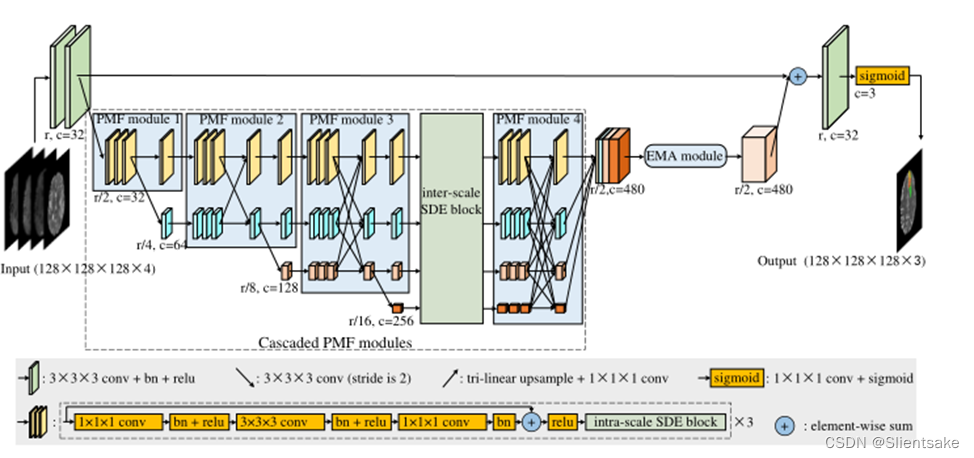

图3所示。HNF-Netv2的架构。与图2相似,r为原始分辨率,c为feature map的通道数。同时,作者在没有深度信息的情况下显示所有地物图,每个地物图的厚度显示其通道号。与HNF-Net相比,作者在级联PMF模块中进一步增加了尺度间和尺度内的SDE块。

在提议的HNF-Netv2中,作者在级联的PMF模块中部署了尺度间和尺度内的SDE块。如图3所示,作者在PMF模块的每个卷积分支内部构造尺度内的SDE块。同时,为了控制计算复杂度,作者只在第3个PMF模块和第4个PMF模块之间插入一个尺度间的SDE块。现在作者将深入研究这些关键组件的细节。

尺度间SDE模块采用PMF模块全连接融合块部署,结构如图4 (a)所示。作者首先对规模n(当前PMF模块中规模最小的分支)的特征应用一个全局平均池(GAP)层,获得具有高度语义信息的全局上下文。然后,作者将得到的特征分别上采样到PMF模块各分支的分辨率。考虑到上采样特征的空间信息较差,作者使用1×1×1卷积层将信道数减少到1,然后将其与高分辨率特征连接。在此设置下,作者可以在减少对原始空间信息破坏的同时,在高分辨率特征中增加全局语义识别。不同于inter-scale端模块,intra-scale端块每个回旋的分支及模块的内部构造与图4中所示的结构(b)。作者还利用一个缺口层生成全局上下文的特性和应用两个1×1×1卷积层调整频道号码。与基于cnn的分类网络的预测层相似,获得的全局特征从各个空间位置收集信息,具有较强的语义信息。因此,作者可以利用这些全局特征对输入的高分辨率特征进行重新加权,从而进一步增强全局语义识别能力。在之前的工作[10,9]之后,作者最终将多尺度增强特征串联起来作为EMA模块的输入。